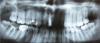

Xevus Опубликовано 23 сентября, 2010 Автор Поделиться Опубликовано 23 сентября, 2010 (изменено) Ну я не думал что от рентгена в данной ситуации есть толк, но ок, выложил. Вопрос в том что делать. Изменено 23 сентября, 2010 пользователем Xevus Ссылка на комментарий

DokDent Опубликовано 21 октября, 2010 Поделиться Опубликовано 21 октября, 2010 Недавно заказал для эксперимента межзубные ершики CuraProx. Сегодня забрал с почты и для эксперимента попробовал первый раз. Прикольно Но речь немного о другом - после чистка промежутка между 6 и 7 зубами сверху ершик вышел пахнущим совершенно отвратительно. История вопроса - года три назад мне диагностировали начальную стадию парадонтита, чистили карманы, накладывали повязки. С тех пор я улучшил свою гигиену, раз в полгода хожу на чистку, последняя вообще была неделю назад. Парадонтолога последний раз видел в декабре, она сказала что состояние отличное.Xevus,вопрос №1:пользуетесь ли вы межзубными нитями?вопрос№2:как нить проходит между этими зубами-с лёгким усилием или свободно?вопрос№3:нет ли подвижности 7-го зуба? Судя по снимку нет плотного коннтакта между этими зубами. Ссылка на комментарий